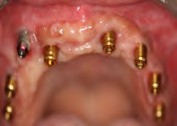

Fig 1. In the pathogenesis of peri-implantitis, inflammatory cell infiltrate enters the connective tissue.

Figure 1

Fig 5. View of a radiograph taken of an implant in September 2009.

Figure 5

Fig 6. To demonstrate how rapidly peri-implantitis bone loss occurs, a radiograph of the same implant shown in Fig 5 taken 3 years later (left) shows significant bone loss, and the photograph (right) shows soft-tissue loss.

Figure 6